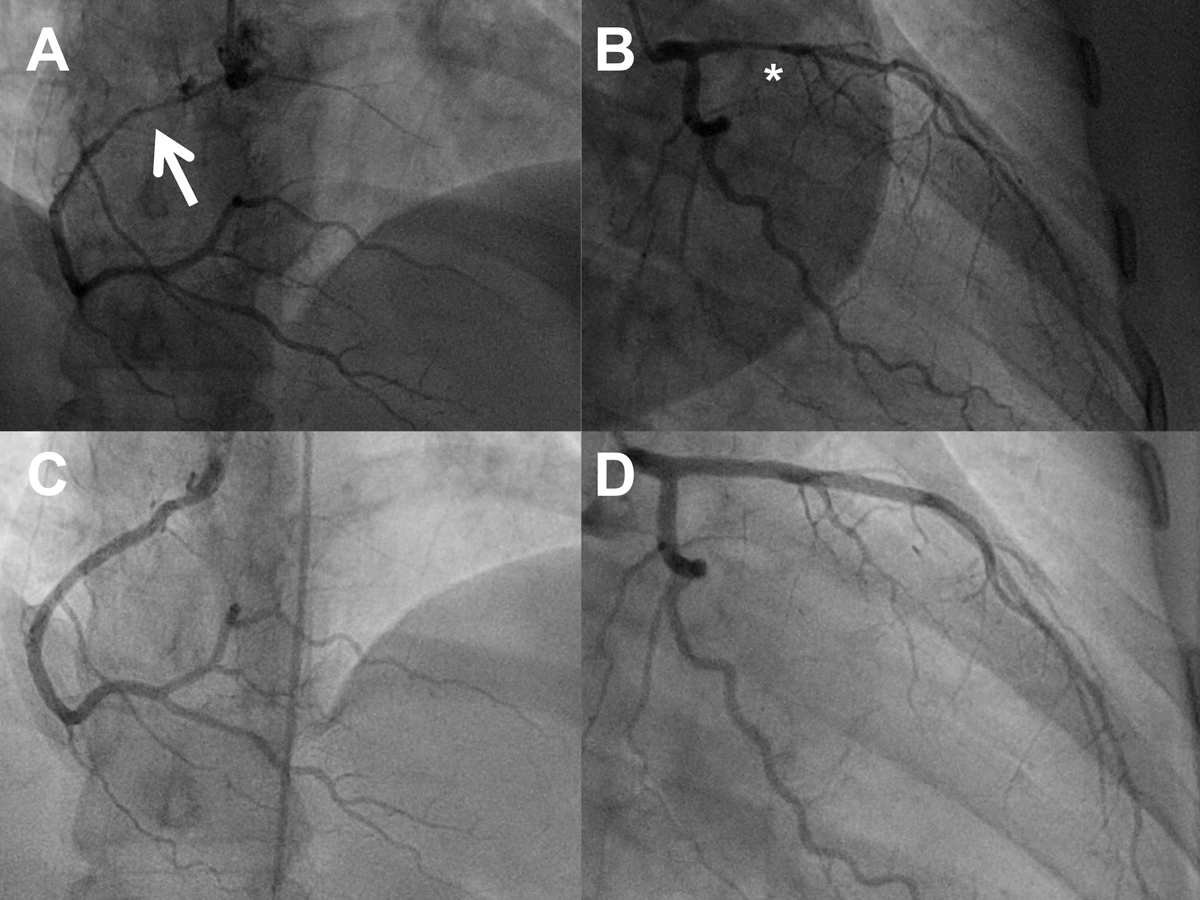

Figure 3 Serial angiograms of a 41-year-old woman (postpartum) with spontaneous coronary artery dissection (SCAD) of the right coronary artery (RCA; panel A, cranial view, arrow pointing to the dissection) and SCAD of the left anterior descending artery (LAD) eight days later (panel B, right anterior oblique 30°/caudal 20° view, asterisk highlighting the dissection). Panels C and D: repeat angiogram after 6 months showing healing of the dissections (same projections; see also Table 4)